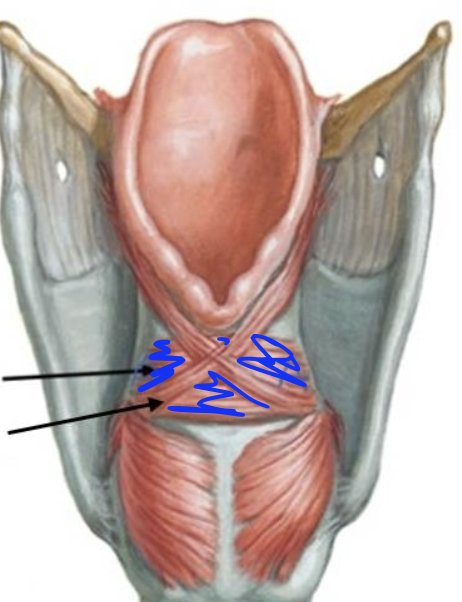

What is this muscle?

Transverse arytenoid (adduct VF)

What is this muscle?

Oblique arytenoid (pull apex medially, assist in adducting VF)